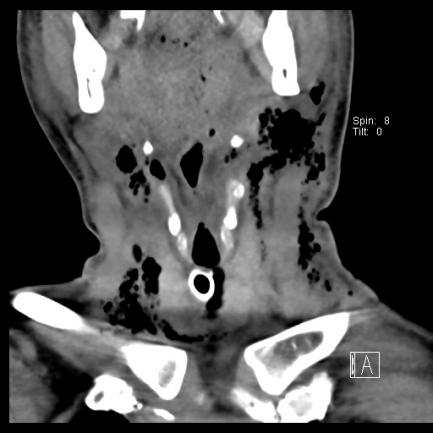

抢救室值班医师当机立断请耳鼻喉科急会诊,此时急诊检查结果回报:血常规:WBC(白细胞计数) 17.9*10^9/L;CT示纵隔、颈部及颌下软组织内积气影。

▲治疗前颈部(冠状位),胸部(轴位)

耳鼻喉科蒋锐主任会诊后考虑口腔颌面、颈部、纵隔多发感染导致的喉梗阻及感染性休克,局部穿刺得脓后更明确了诊断。